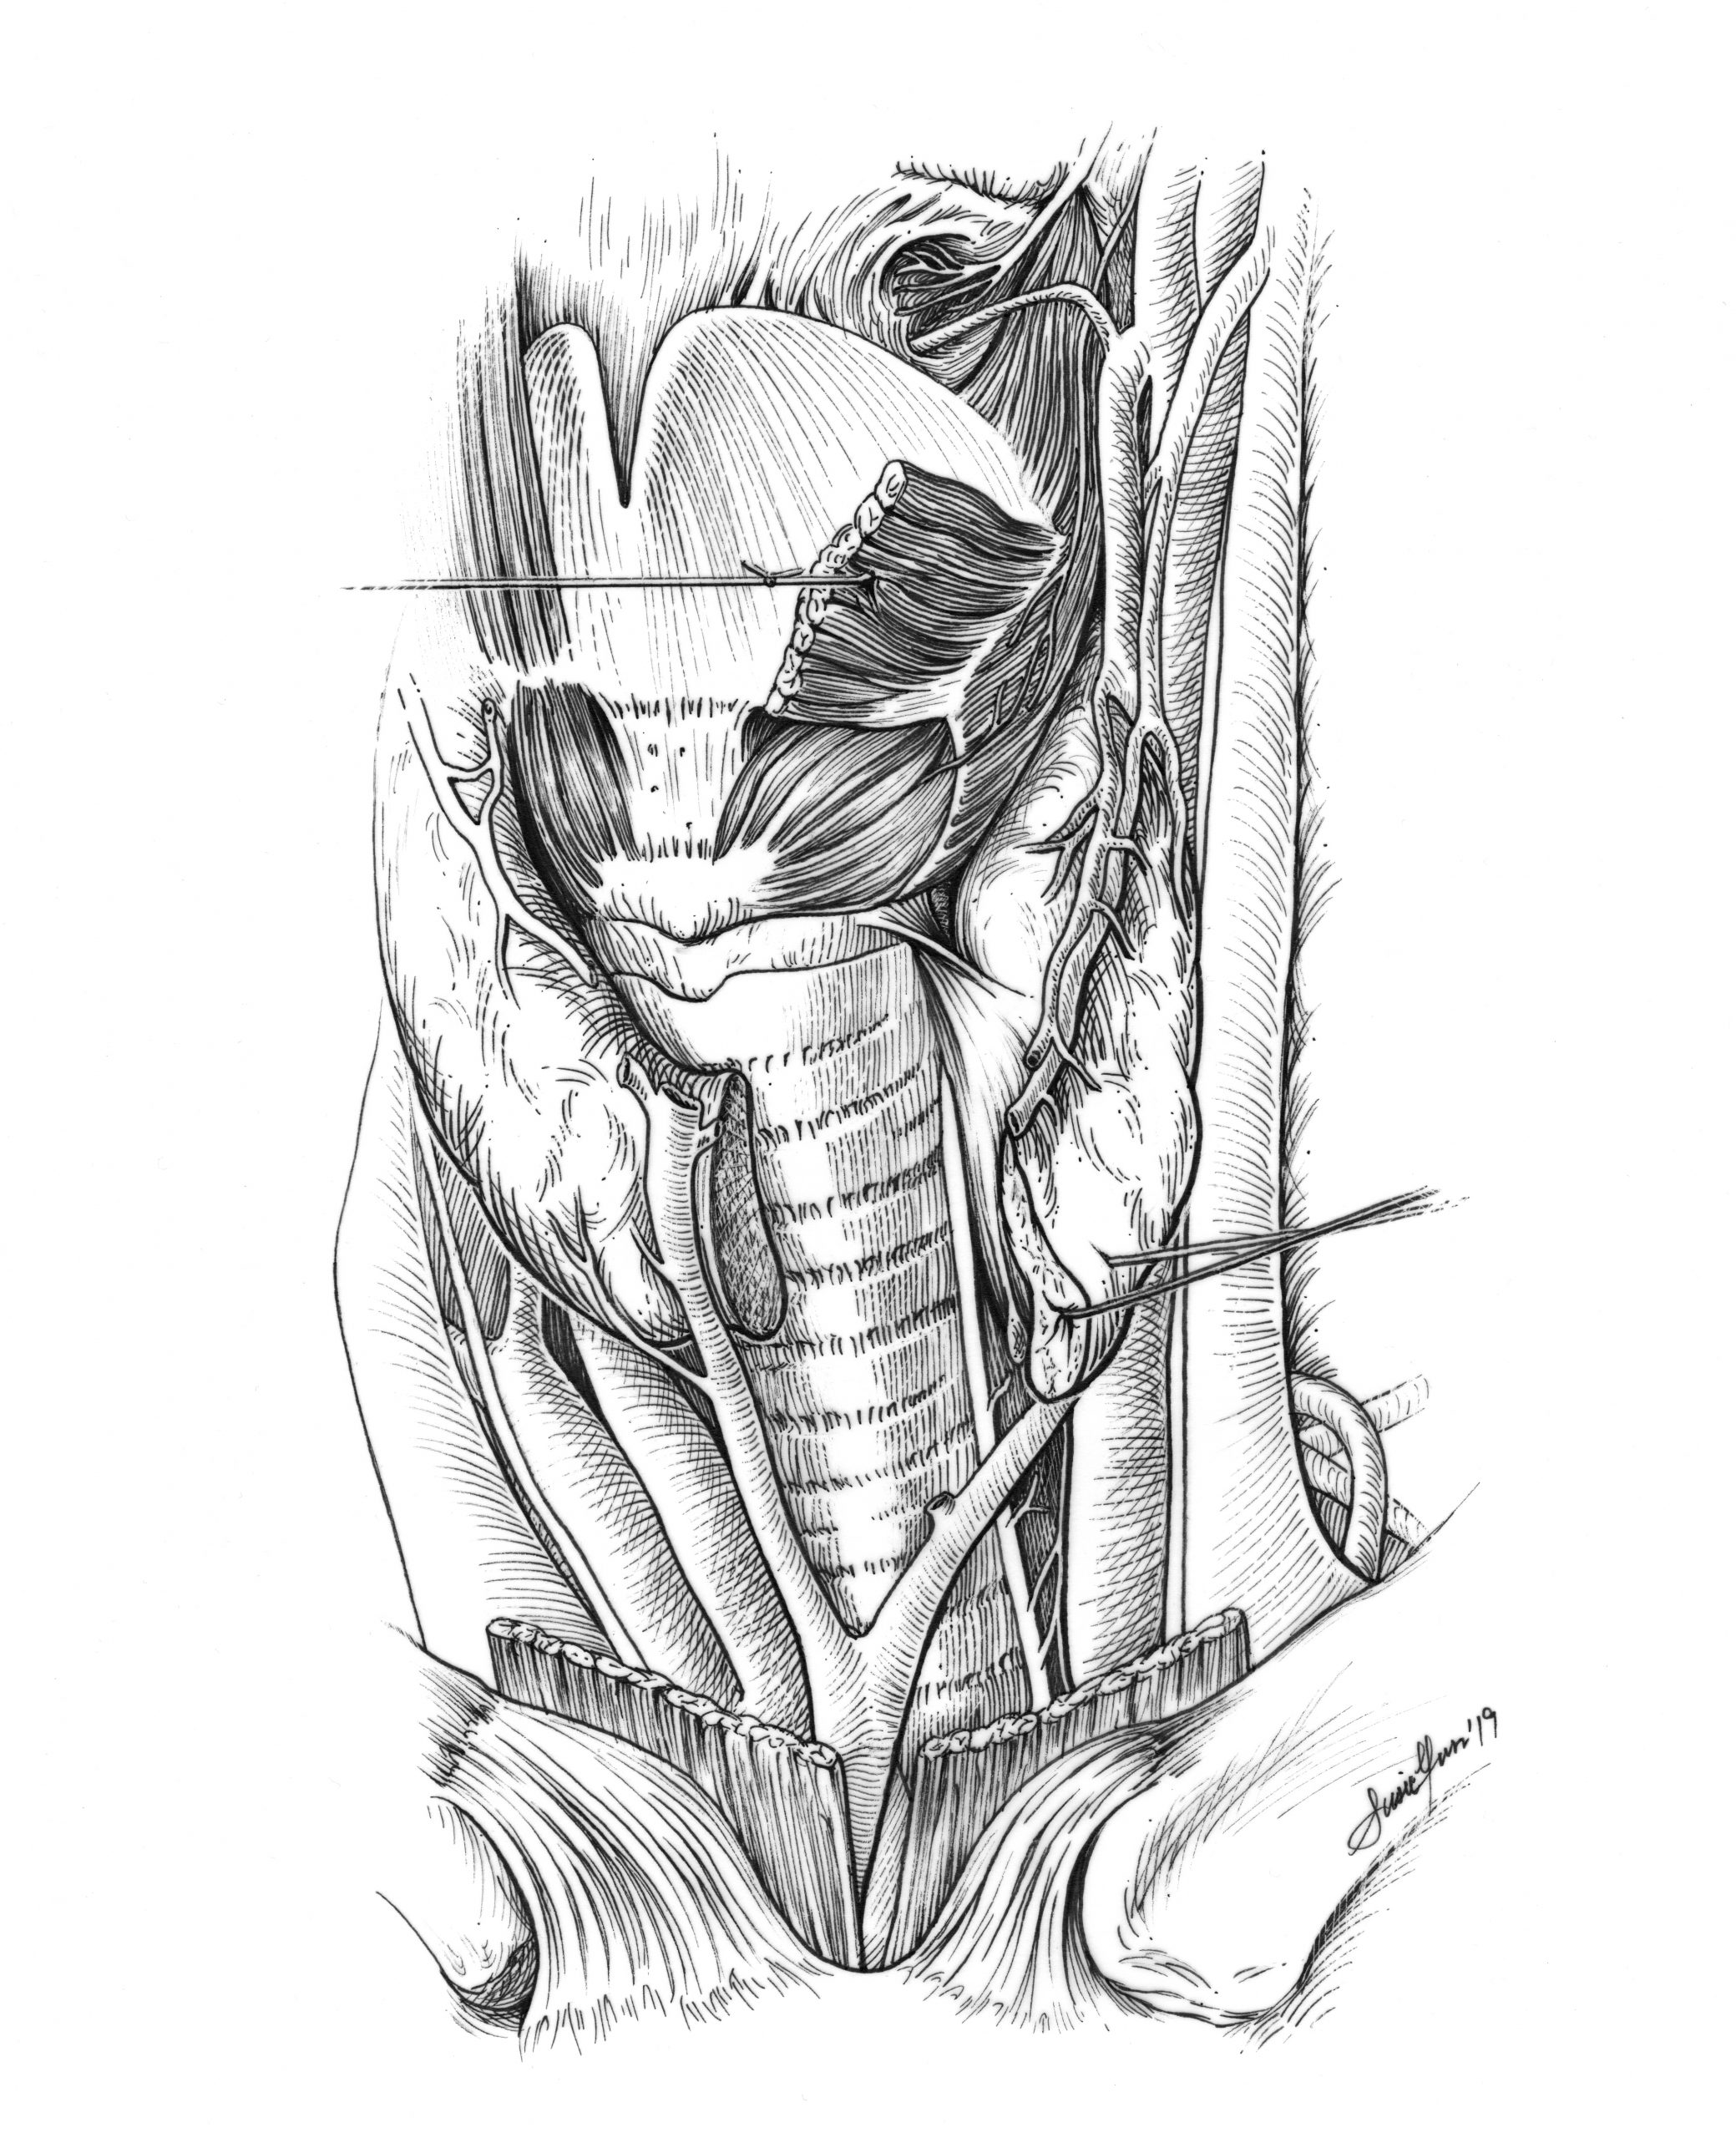

- Anatomy illustration translation from tone

- Anatomy illustration (from cadaver dissection)

Student Artwork